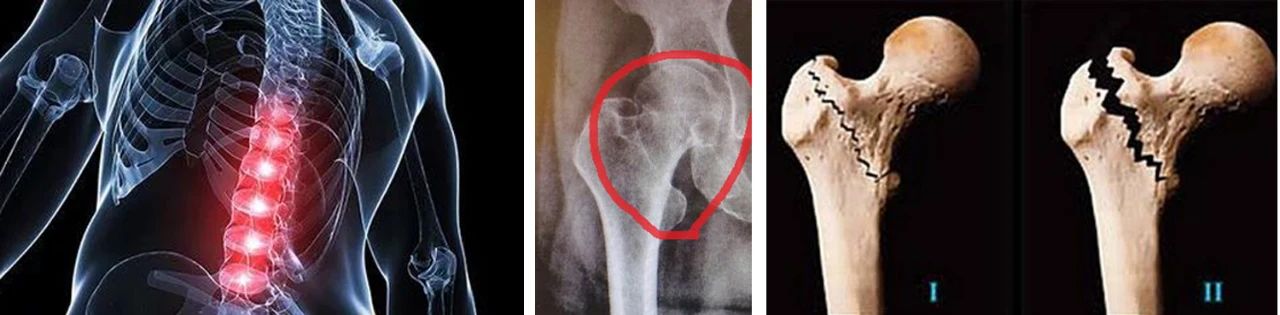

老年人摔倒时,有三大部位最容易发生骨折,分别是腰椎压缩性骨折、髋部骨折(股骨颈或转子间骨折)和桡骨远端骨折。

河北省老年病医院骨一科针对老年人跌倒所致的脊柱压缩骨折,老年四肢骨折,以及常发的老年髋部骨折等,应用微创、手术、固定等多种方法,帮助老年患者快速康复,最大程度提高老年患者生活质量。